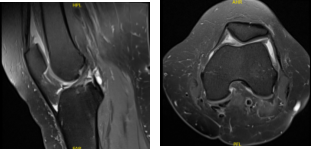

There are no acute fractures. She also presented an MRI results that showed trace joint effusion. Tiny popliteal cyst. Minimal lateral patellar shift. Degenerative medial and lateral meniscus tears as detailed above. Minimal osteoarthritis in the medial and lateral joint compartment of the left knee.

MRI Left knee non-contrast